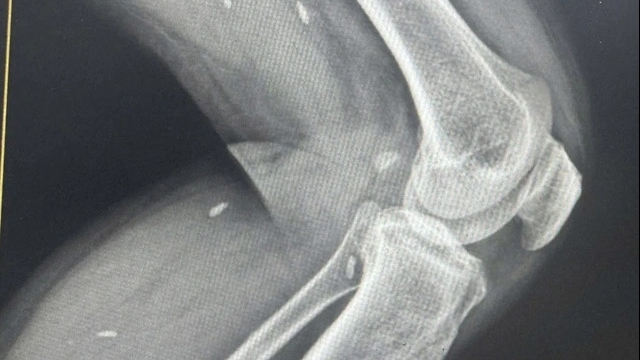

| Hai bệnh nhân người Anh tiếp xúc với nhân viên của Điện Máy Xanh tại TP Đà Nẵng khiến một người bị dương tính với virus SARS-CoV-2 (Ảnh: V.Q) |